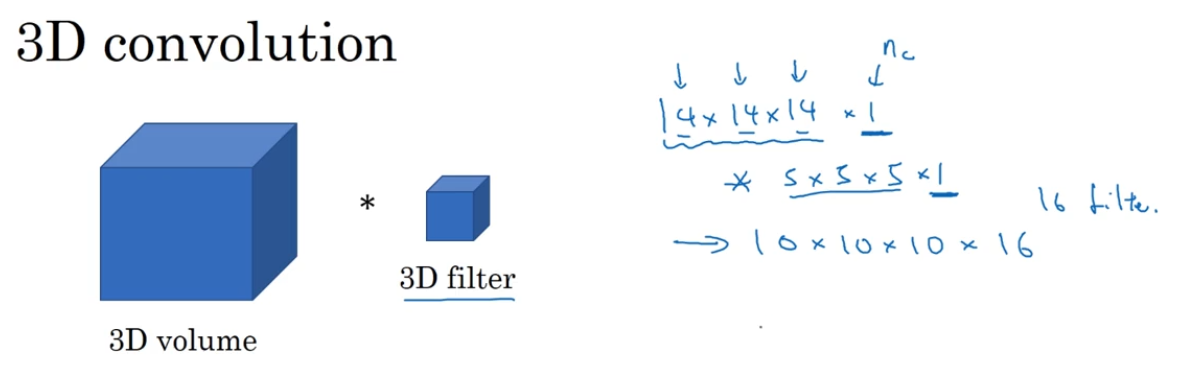

如果你想要在3D扫描或CT扫描中应用卷积网络进行特征识别,你也可以从3D卷积的第一行开始,为了简单起见,如果你有一个3D对象,比如说是14×14×14

技术上来说你也可以再×1(通道数),前面的14×14×14仅仅只是一个3D模块,如果你使用16个过滤器,那么输出就是10×10×10×16

如果下一层的过滤器使用5×5×5×16(通道数和往常一样匹配)如果你有32个过滤器,输出就是6×6×6×32